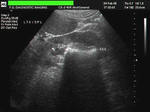

Kidney Stone

This patient had pain in the right lumbar region. Sonography of the kidneys reveals an markedly echogenic lesion in the lower calyx of right kidney. An acoustic shadow is seen posterior to the lesion. These ultrasound images are diagnostic of a renal calculus (measuring 15 x 10 mm. in size) in the lower calyx. Absence of pelvicalyceal dilatation suggests that there is no obstruction to urinary flow. It is always useful to scan the renal calculus and kidney in two planes to get an accurate measurement in two axis.  Ultrasound images taken using Pie Scanner 100 Falco, by Dr. Joe Antony, MD, Cochin, India.